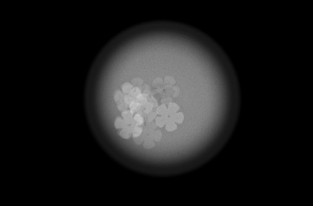

圧迫の必要性

厚みのある乳房の中にはたくさんの乳腺や脂肪などが重なって存在しています。

これらを均等に伸ばし組織同士の重なりを分離することで、小さなしこりや石灰化の粒をより見つけやすい画像にすることができます。

*実際に乳房を圧迫する時間は1枚の撮影で数十秒程度です。

画像1枚目:圧迫なし、画像2枚目:圧迫あり

水風船の中に花型のビーズをいれました。

厚みを約半分にしたことで、形がはっきり見えるようになります。